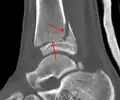

| Fracture of both sides of the ankle with dislocation as seen on anteroposterior X-ray. (1) fibula, (2) tibia, (arrow) medial malleolus, (arrowhead) lateral malleolus | |